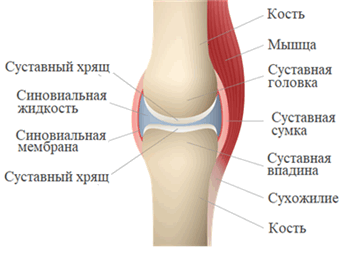

Сустав (синовиальное соединение - греч. sýn - вместе + лат. ovum - яйцо) - подвижное соединение костей скелета. Наука о суставах - артрология (греч. arthron - сустав + logos - учение). Связки - плотные образования из соединительной ткани - укрепляют сустав изнутри и снаружи (связки бывают внутрисуставными и внесуставными).

Поверхности костей в суставе (называемые - суставные поверхности) покрыты гиалиновым хрящом, который снижает трение между костями, выполняет амортизирующую функцию - равномерно распределяет давление.

Суставная сумка (капсула) крепится к суставным поверхностям или в их близи, окружает суставную полость (щелевидное пространство). Суставная сумка изнутри покрыта синовиальной оболочкой, которая секретирует синовиальную жидкость. Синовиальная жидкость заполняет полость сустава, питает сустав, увлажняет его, устраняет трение суставных поверхностей.

Суставные поверхности соответствуют друг другу по форме и покрыты гиалиновым хрящом. Суставная сумка образует герметичную полость с синовиальной жидкостью. Это способствует скольжению и защищает кость от стирания.

- суставные поверхности костей;

- суставную сумку;

- суставную полость;

- суставную (синовиальную) жидкость.